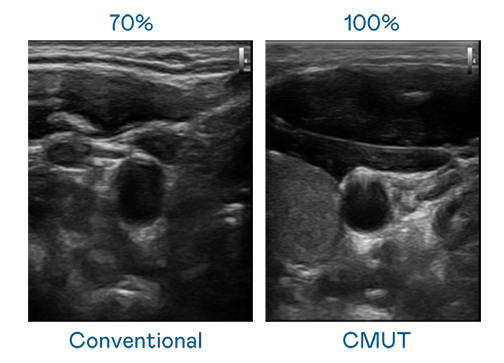

CMUT 技术是一种用电容式微机电元件来产生超音波讯号的技术。与传统 PZT 压电式技术相比,CMUT 频宽增加 30%,更宽频的超音波讯号让影像解析度大幅提升,是实现高影像品质医疗超音波扫描、促进精准医疗发展的关键技术。

超音波影像的解析度高低,首先取决于探头能发出的讯号频宽。永利集团304 CMUT 可提供高清晰的超音波讯号,提供高频宽、高灵敏度、影像纹理细节更高的超音波影像,协助医护人员缩短影像判读时间及利用精准的医疗影像进行诊断。